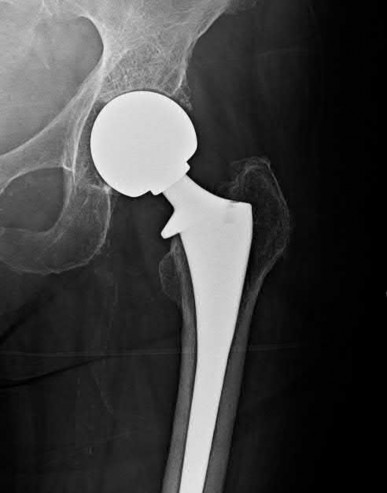

A 76-year-old male community ambulatory presented to clinic complaining of pain in the left groin that has been persistent for the last 8 months. Radiographs obtained from clinic are seen in Figure A. You suspect a femoral neck nonunion and obtain a CT scan which confirmed it. Which of the following statements is true?

A total hip arthroplasty (THA) after nonunion of a femoral neck fracture would provide the best long term outcomes in a 76-year-old male who is a community ambulator.

After nonunion of a femoral neck fracture, hemiarthroplasty and THA are good salvage option for the physiologically older patients. When deciding between these two options, THA is better for active and cognitively intact patients. THA is also indicated in patients with radiographic evidence of degenerative disease about the acetabulum. Hemiarthroplasty is advocated for patients who are older and less active.

Yang et al. retrospectively investigated the risk factors for nonunion in patients treated with cannulated screws. They reviewed 202 patients who had femoral neck fractures and were treated with internal fixation with cannulated screws. They identified that triangle configuration, displaced fracture, borderline or unacceptable reduction, and increased screw shaft subchondral purchase over the femoral neck were all risk factors for nonunion after internal fixation.

Inverted triangle configuration was found to increase rate of union.

Archibeck et al. retrospectively reviewed the outcomes of 102 THAs after failed internal fixation for a hip fracture (including both femoral neck and intertrochanteric). They concluded that the conversion of failed hip internal fixation has elevated risks compared to a primary THA, however, it may still be successful. The biggest concern for these patients postoperatively are periprosthetic fracture and dislocation.

Figures and Illustrations:

Figure A is an AP pelvic radiograph demonstrating a nonunion of a femoral neck fracture after suboptimal fixation with 3 cannulated screws in a triangle configuration.

Illustration A is an AP radiograph of the left hip in this patient following conversion to THA.

Illustration B is a radiograph demonstrating a valgus osteotomy. Illustration C shows an example of a femoral neck nonunion with varus malreduction.